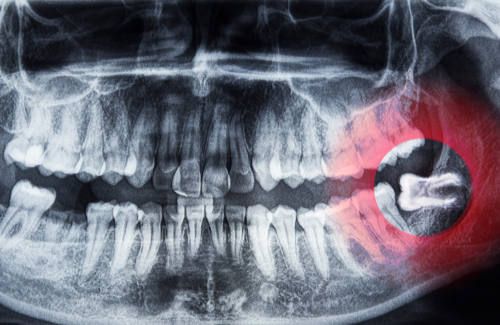

親知らずが虫歯かも?痛みや腫れの原因と抜くべきケースを解説

親知らずは、まっすぐ生えずに斜めや横向きに生えてくることがあります。このような生え方をしていると、歯と歯ぐきのすき間や、手前の歯との間に食べかすや歯垢がたまりやすくなります。

半分だけ歯ぐきから出ている親知らずでは、見えている部分だけでなく歯ぐきのふちにも汚れがたまりやすく、虫歯だけでなく炎症の原因になることもあります。親知らずの生え方によって虫歯のリスクは高くなるため、一度状態を確認しておくと安心です。

親知らずの抜歯を考えやすいのは、虫歯が深く進んでいる場合や、横向き・斜め向きに生えていて汚れがたまりやすい場合です。

特に、神経まで虫歯が進んでいると治療が複雑になりやすく、親知らずは根の形も複雑なことがあるため、保存が難しくなるケースがあります。